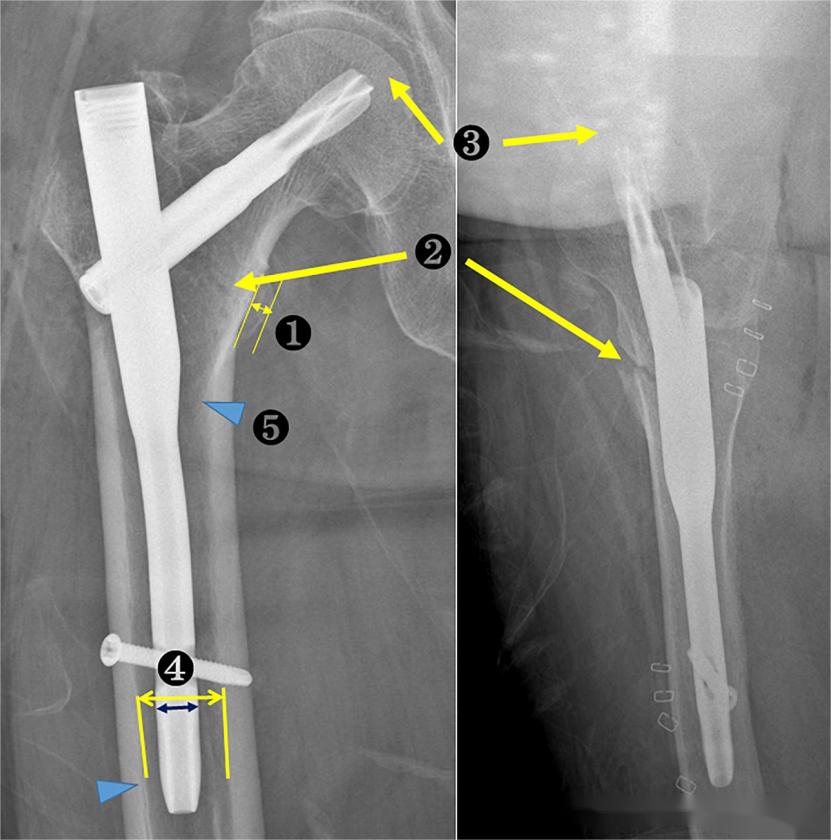

The study included 191 cases of unilateral intertrochanteric fractures, all treated with PFNA-II internal fixation. When the lesser trochanter was fractured and detached, a 200mm short nail was used; when the lesser trochanter was intact or not detached, a 170mm ultra-short nail was used. The diameter of the main nail ranged from 9-12mm. The main comparisons in the study focused on the following indicators:

1. Lesser trochanter width, to assess whether the positioning was standard;

2. Relationship between the medial cortex of the head-neck fragment and the distal fragment, to evaluate the quality of reduction;

3. Tip-Apex Distance (TAD);

4.Nail-to-canal ratio (NCR). NCR is the ratio of the main nail diameter to the medullary canal diameter on the distal locking screw plane.